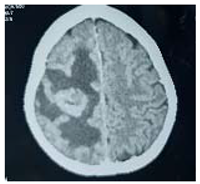

#Case 1:

This is 18years Sudanese young female, university student, an otherwise healthy before, presented to neurosurgery emergency unit with history of rabidly progressing headache for 6 months duration, few weeks before her appearance she exhibit visual blurring that end in decrease visual acuity in both eyes, she has inability to walk steady.

Neurological examination, revealed conscious patient, with just perception to light and there was increase tone and exaggerated reflexes on both lower limbs.

Operation: Before the decision of surgery, we talked to the patient and her family clearly about the surgery complications and post operative outcome. Through left tempro- parito-occipital craniotomy, the tumor was macroscopically totally resects. It was sub cortical, well circumscribed ill define capsule, extended deeply to the underlining temporal horn of the lateral ventricle .Dural graft was taken from the tempralis fascia and was closed in water tide.

Patient was fully recovered from anesthesia and was taken to the ICU on nasal oxygen mask.

Histopathology

Brain tubeclomata ( extra pulmonary tuberculosis)

Patient was put on anti-tuberculosis according to the international protocol, and discharged free of headache, can see objects.